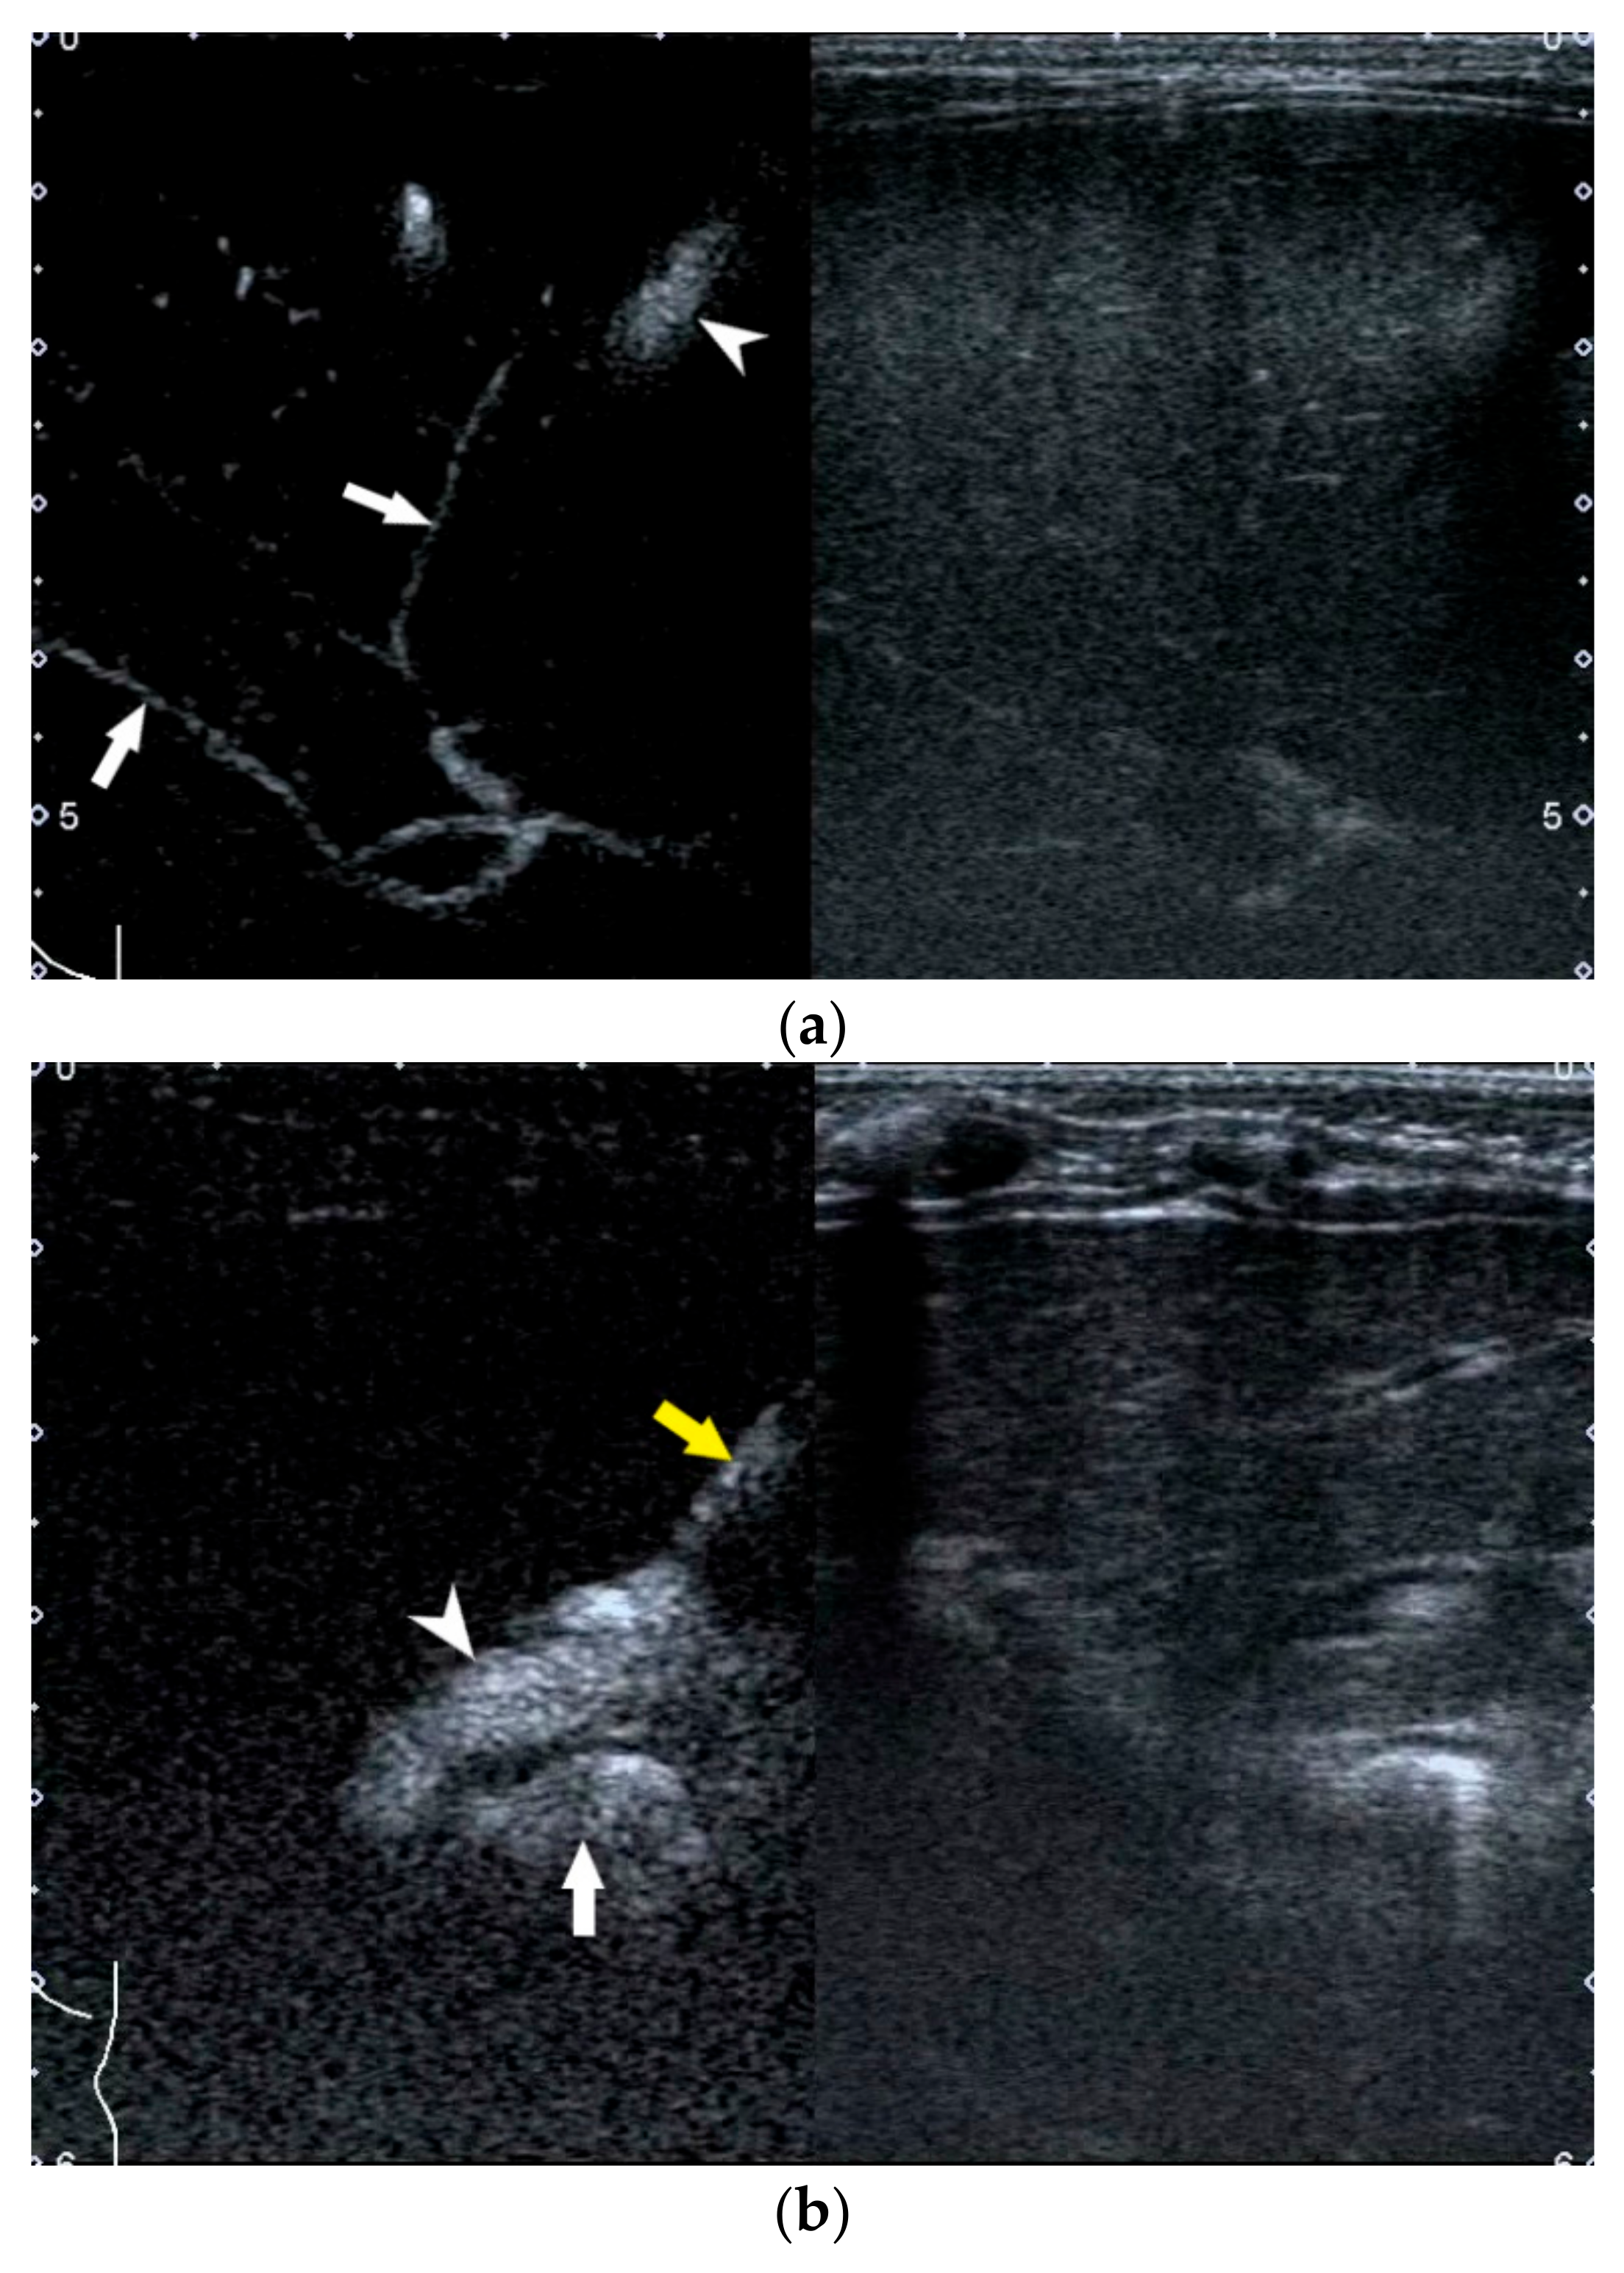

4. US-Guided Percutaneous Cholecystocholangiography with Microbubbles

- Zhou, L.-Y.; Chen, S.-L.; Chen, H.-D.; Huang, Y.; Qiu, Y.-X.; Zhong, W.; Xie, X.-Y. Percutaneous US-guided Cholecystocholangiography with Microbubbles for Assessment of Infants with US Findings Equivocal for Biliary Atresia and Gallbladder Longer than 1.5 cm: A Pilot Study. Radiology 2018, 286, 1033–1039. [Google Scholar] [CrossRef]

- Lee, S.Y.; Kim, G.C.; Choe, B.-H.; Ryeom, H.K.; Jang, Y.-J.; Kim, H.J.; Park, J.Y.; Cho, S.-M. Efficacy of US-guided Percutaneous Cholecystocholangiography for the Early Exclusion and Type Determination of Biliary Atresia. Radiology 2011, 261, 916–922. [Google Scholar] [CrossRef] [Green Version]